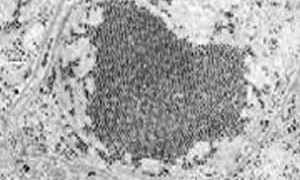

ウシ(牛)の病気  ウイルス

ウイルス  ウイルス

ウイルス  ウイルス